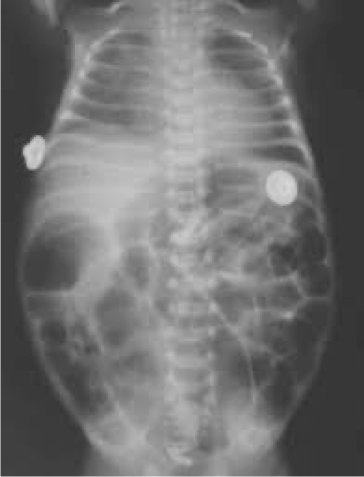

- Dilated loops,

- thickened bowel walls,

- pneumatosis intestinalis (air in intestinal walls),

- pneumoperitoneum; indicate perforation (emergency requiring surgical intervention),

- portal gas (present in the portal venous system,

- considered to be a poor prognostic sign).

inflamed, necrosis ⇒ Perforation everywhere

dark circles air in intestinal wall

Air in portal gas